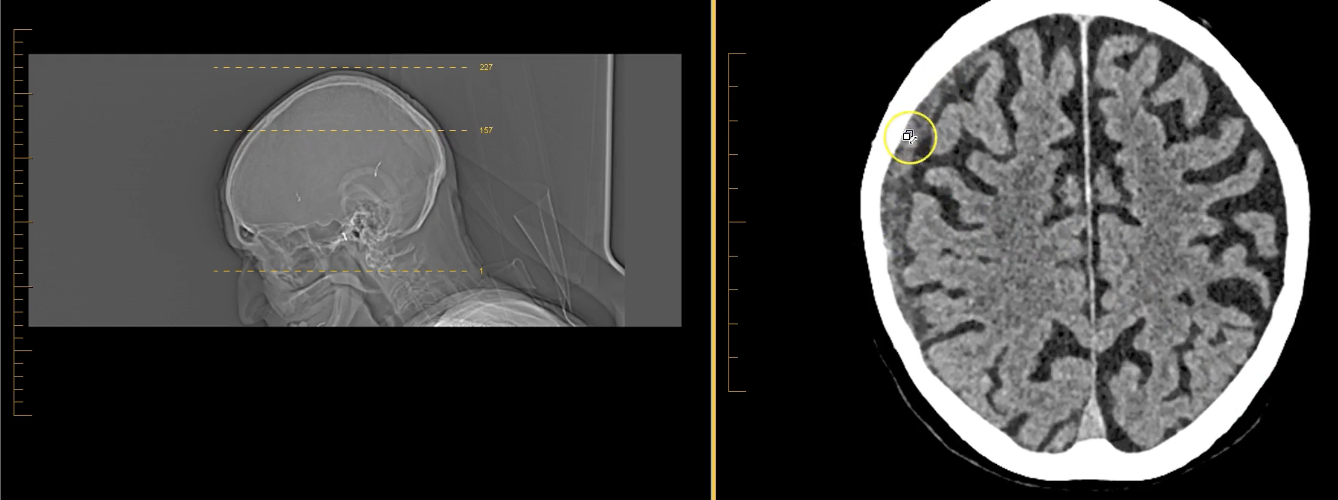

term image

lateral ventricles